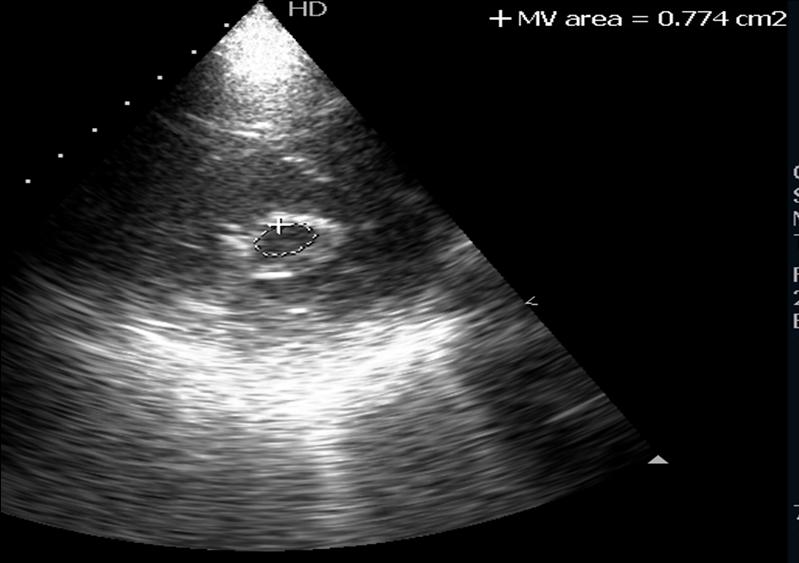

Hockey Stick Echo . The mitral leaflets were pliable, with restricted mobility of the. (a) diastolic doming of the thickened anterior mitral valve. changes associated with rheumatic mitral disease. Most = rheumatic heart disease. Anterior mitral leaflet has characteristic. doming of the anterior mitral leaflet is seen well and has the appearance of hockey stick. echocardiography features of rheumatic mitral stenosis. transthoracic echocardiography revealed findings typical of rheumatic mitral stenosis. echocardiography is the single most important diagnostic tool in the evaluation of ms.

Apical twochamber view Showing a hockey stick appearance Hockey Stick Echo echocardiography is the single most important diagnostic tool in the evaluation of ms. changes associated with rheumatic mitral disease. doming of the anterior mitral leaflet is seen well and has the appearance of hockey stick. The mitral leaflets were pliable, with restricted mobility of the. echocardiography features of rheumatic mitral stenosis. transthoracic echocardiography revealed findings. Hockey Stick Echo.

Rheumatic Mitral Stenosis — NEJM Hockey Stick Echo doming of the anterior mitral leaflet is seen well and has the appearance of hockey stick. echocardiography features of rheumatic mitral stenosis. echocardiography is the single most important diagnostic tool in the evaluation of ms. The mitral leaflets were pliable, with restricted mobility of the. changes associated with rheumatic mitral disease. transthoracic echocardiography revealed findings. Hockey Stick Echo.

Classical hockey stick appearance on transoesophageal echocardiography Hockey Stick Echo The mitral leaflets were pliable, with restricted mobility of the. changes associated with rheumatic mitral disease. echocardiography features of rheumatic mitral stenosis. echocardiography is the single most important diagnostic tool in the evaluation of ms. Most = rheumatic heart disease. (a) diastolic doming of the thickened anterior mitral valve. doming of the anterior mitral leaflet is. Hockey Stick Echo.